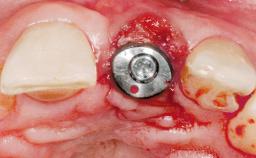

Immediate Flapless Placement of an Implant in a Maxillary Left Central Incisor Site

A 42-year-old female patient was referred to our clinic at the School of Dentistry of the University of São Paulo in November 2004, presenting a deficient restoration in the upper left central incisor. The clinical examination revealed no gingival retraction or any signs of gingival inflammation and, therefore, previous periodontal treatment was not considered. The patient presented a high lip line at full smile and a thin tissue biotype. This combination characterized a high-risk situation from an anatomic point of view, which required careful preoperative planning and cautious surgical execution.

Type of Implants One-Piece